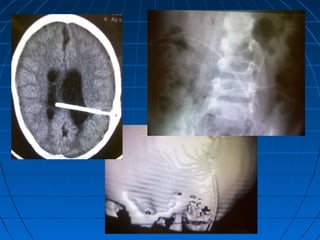

При поступлении больных с признаками

дисфункции ликворошунтирующей

системы проводится стандартное

дообследование в экстренном порядке:

- КТ головного мозга,

-шунтография,

-УЗИ брюшной полости (наличие свободной

жидкости),

-пункция клапана с исследованием ликвора